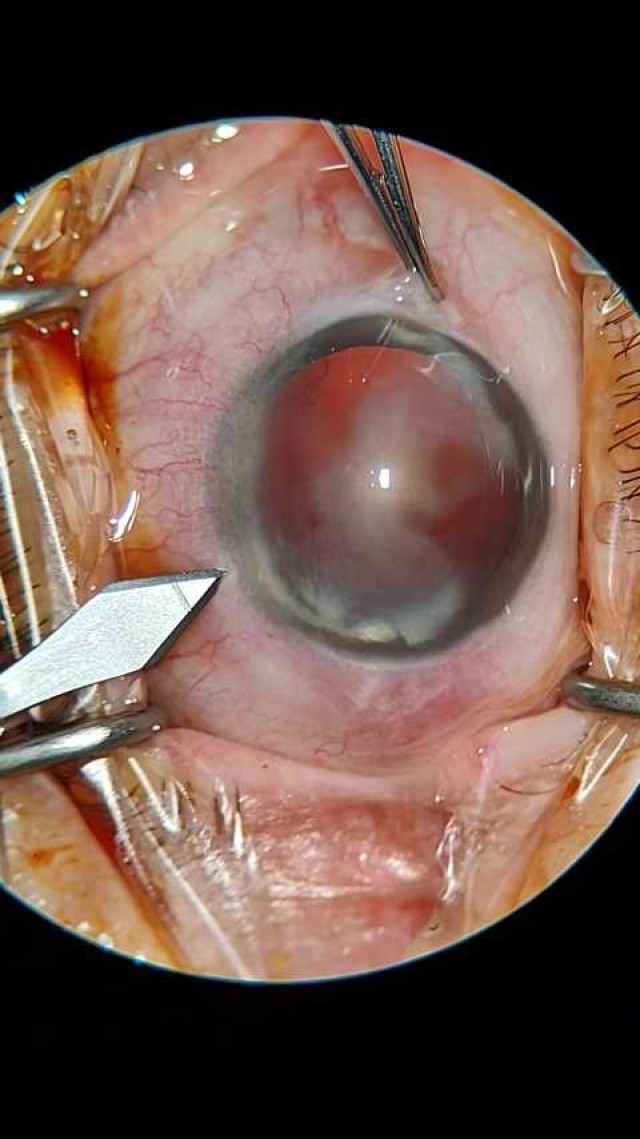

大瓜:湖南省人民医院副院长出轨眼科主任?

号外号外,湖南省人民医院副院长祖雄兵和眼科主任医师曾琦被指存在不正当关系,并有不雅视频传出。对此,医院工作人员回应:组织正在调查,请给医院宣传部门联系。当地卫生健康委员会对此回应:暂未接到相关的信访反映。祖雄兵为湖南省人民医院副院长,泌尿外科学科带头人。曾琦,博士,主任医师,硕士研究生导师。现任湖南省人民医院眼科副主任、眼科一病区主任,湖南省卫生健康高层次青年骨干人才,湖南省预防医学会眼病防治专业委员会主任委员、湖南省女医师协会眼科专业委员会主任委员、湖南省医学会眼科学专业委员会防盲学组副组长、湖南省医学会眼科学专业委员会眼外伤及职业病学组副组长、湖南省医学会眼科学专业委员会白内障学组副组长、